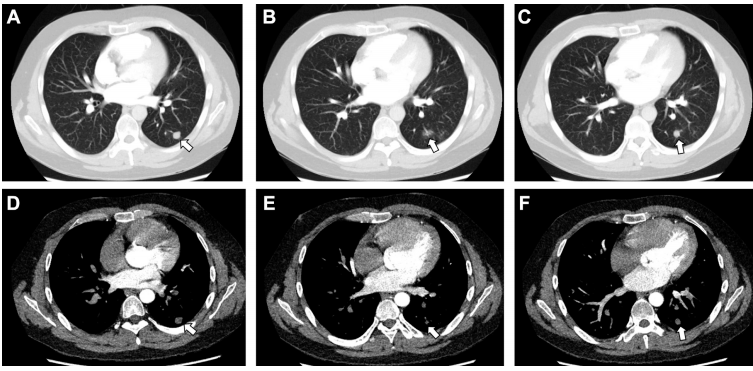

CT 肺动脉造影排除了肺栓塞,该检查显示左肺下叶有两个无强化结节,一个呈圆形且有实性成分,另一个有空洞及晕征(下图)。

上图 A - F 为胸部 CT 肺动脉造影图像。A 图,左肺下叶见一个结节(箭头所示);B 图,左肺下叶另一个结节周围有空洞及晕征(箭头所示);C 图,左肺下叶的另一个结节(箭头所示);D - F 图,两个结节均无强化(箭头所示)。